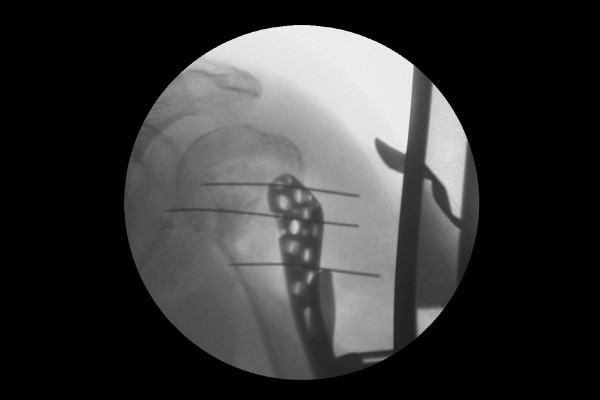

실시간 X-RAY인 C-ARM을 이용하여 실시간으로 확인하며 임시 고정한 후

강하게 스크류 금속판 고정을 합니다.